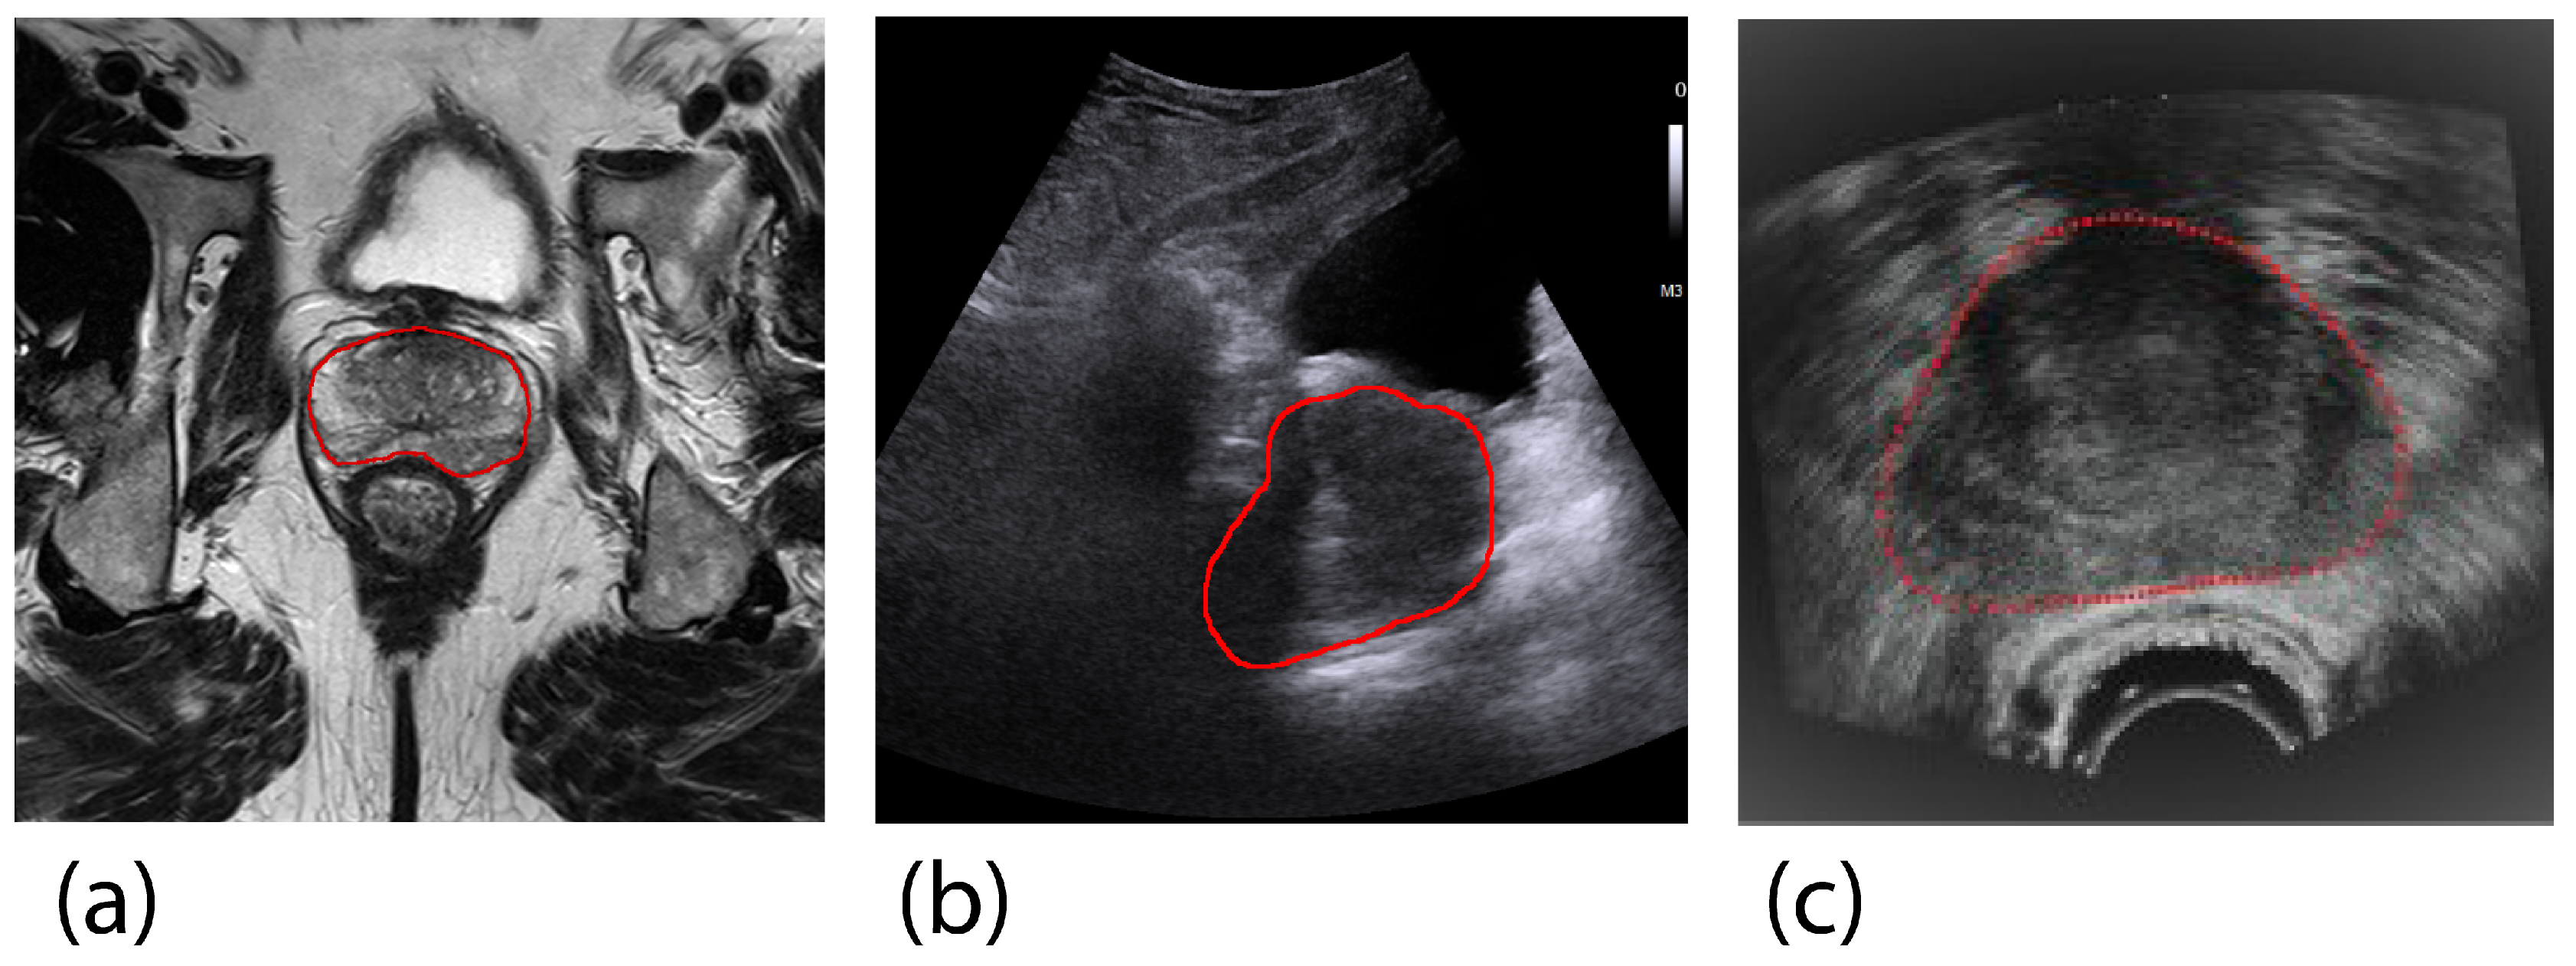

In clinical settings, imaging modalities such as computed tomography (CT), magnetic resonance imaging (MRI), and ultrasound (US) are used to evaluate prostate malignancy and volume. Each imaging modality has unique characteristics that determine its suitability based on the clinical context. MRI-based PV estimation is considered the gold standard due to its superior signal-to-noise ratio [7]. However, transrectal ultrasound (TRUS) is more commonly used in clinical practice because it is cost-effective, portable, and allows for rapid PV estimation [7,8]. Transabdominal ultrasound (TAUS) is another viable option, often preferred for its non-invasive and more comfortable approach [9]. Figure 1 illustrates examples of prostate images obtained by TAUS, TRUS, and MRI, highlighting the differences among these imaging modalities.

Figure 1. Cross-section examples of the prostate in different imaging modalities in the transverse (axial) plane, where the prostate is manually delineated in yellow. (a) Magnetic Resonance Imaging (gold-standard for prostate volume evaluation), (b) Transabdominal Ultrasound, (c) Transrectal Ultrasound (Adapted from Karimi et al. (2019) [16], with permission from Elsevier).